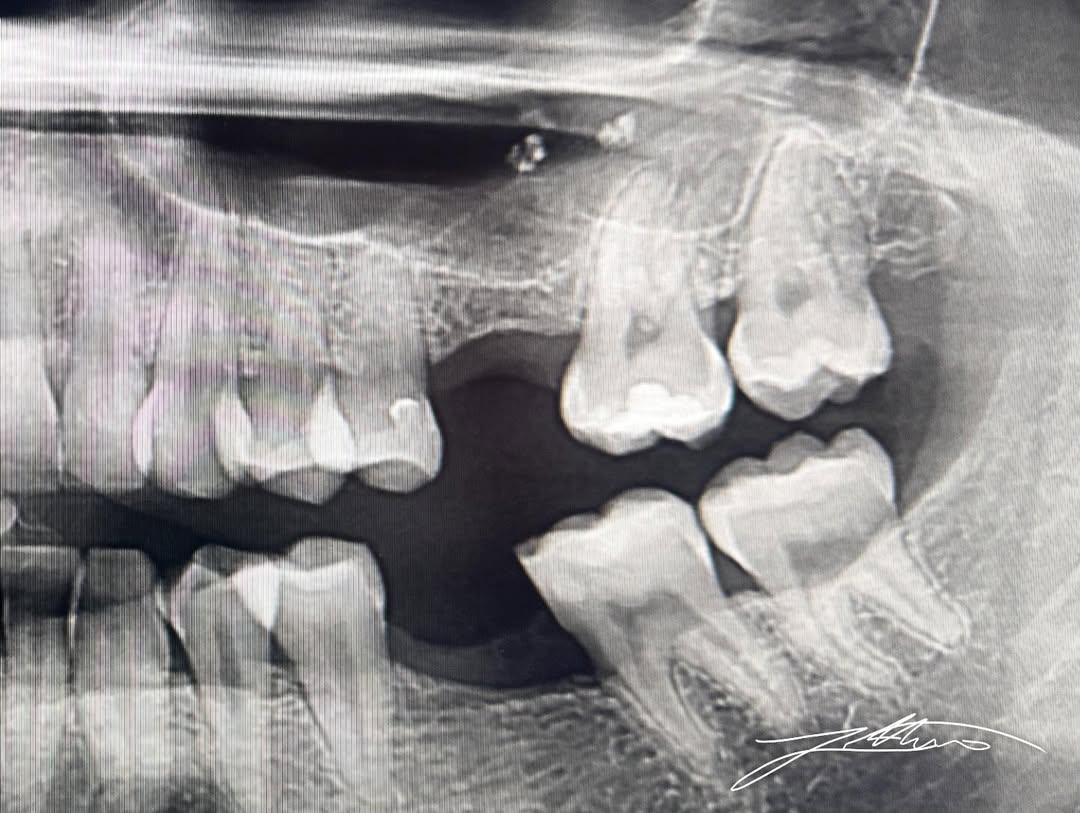

Përshkrimi i rastit klinik Pacienti u paraqit në klinikë me mungesën e elementit dentar 26, duke shfaqur një disponueshmëri kockore vertikale shumë të kufizuar, rreth 2.8 mm, në zonën posterio-superiore të maksilës. Kjo situatë klinike përfaqëson një sfidë të njohur në implantologji, veçanërisht në zonën e sinusit maksilar, ku resorbimi kockor pas humbjes së dhëmbit dhe pneumatizimi progresiv i sinusit reduktojnë ndjeshëm lartësinë e kockës së disponueshme për vendosjen e implanteve dentare.

Pas një vlerësimi të detajuar klinik dhe radiologjik para-operativ, duke përfshirë ekzaminimin CBCT, u përcaktua se alternativa më e sigurt, biologjikisht e respektueshme dhe klinikisht e parashikueshme ishte realizimi i një ngritjeje krestale të sinusit maksilar, e asistuar nga teknologjia Magnetic Mallet, me qëllim rritjen e lartësisë kockore dhe krijimin e kushteve të nevojshme për vendosjen e implantit dentar.